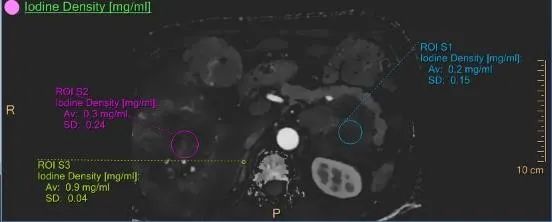

02.在腫瘤診斷方面

彩色光譜CT運用獨特的雙層光譜探測器,擁有優(yōu)質(zhì)的超高清成像技術(shù),能早期發(fā)現(xiàn)隱匿病灶、實現(xiàn)腫瘤的良惡性和精準分期、分級以及腫瘤活性的評估,同時能對多發(fā)病灶的同源性,淋巴結(jié)是否有轉(zhuǎn)移,指導(dǎo)臨床作出個性化、精準的治療方案。